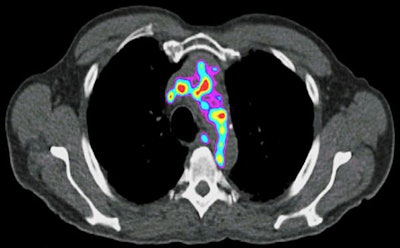

Plaque containing inflammatory cells and proteins is more likely to rupture, so the researchers are designing PET radiotracers to detect signs of inflammation within plaque. For this research, Liu plans to study mice with atherosclerosis and samples of blood vessels from people who have undergone plaque-removal surgery to assess whether the tracers can reliably detect vulnerable plaque.